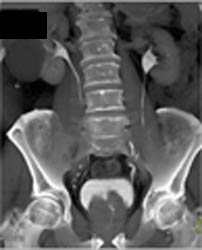

Diagnosis

Clot in Left Atrium